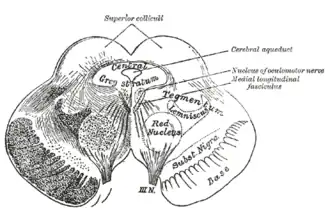

Section through superior colliculus showing path of oculomotor nerve. Periaqueductal gray is the gray area just peripheral to the cerebral aqueduct. | |

Transverse section through mid-brain.

The periaqueductal gray is the gray matter located around the cerebral aqueduct within the tegmentum of the midbrain. It projects to the nucleus raphe magnus, and also contains descending autonomic tracts. The ascending pain and temperature fibers of the spinothalamic tract send information to the PAG via the spinomesencephalic pathway (so-named because the fibers originate in the spine and terminate in the PAG, in the mesencephalon or midbrain).